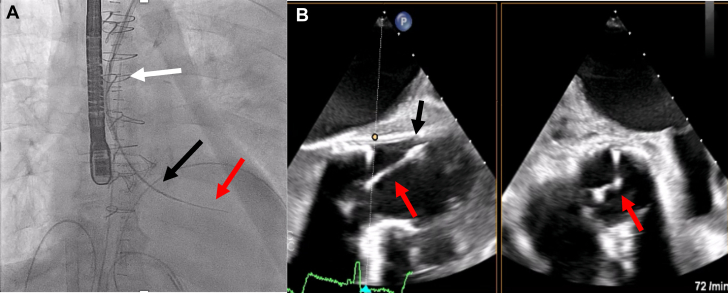

The first challenge was the crossing of functionally closed surgical aortic bioprosthesis. This was managed by three-dimensional navigation using the mother-and-child technique, with a multipurpose diagnostic catheter in a steerable guiding catheter (Agilis, Abbott) under transesophageal echocardiographic guidance. The latter provided clear visualization of the leaflet coaptation positions, allowing targeted, atraumatic crossing (Figure 1).

Figure 1.

Crossing of the Bioprosthetic Aortic Valve

(A) Fluoroscopic image showing the crossing with mother-and-child technique. The white arrow indicates the steerable sheath, the black arrow indicates the multipurpose catheter, and the red arrow indicates the wire. (B) Transesophageal echocardiogram showing the wire crossing. The black arrow indicates the multipurpose catheter, and the red arrow indicates the wire.